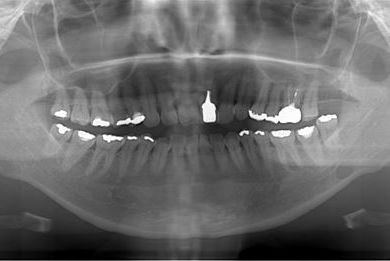

セラミック治療+ラミネートベニア治療

| 主訴 | 虫歯を白い詰め物で治療したい。全体的に歯の色が気になるので、ホワイトニングをしたい。ホワイトニングの効果がなければ、セラミック治療を受けたい。 | ||||||||||||||||||||||||||||||||

| 治療方針 | セラミック治療にて、審美的回復を行う。 | ||||||||||||||||||||||||||||||||

| 治療内容 | ジルコニアオールセラミッククラウン1本(オールセラミック用土台1本)、オールセラミッククラウン9本(オールセラミック用土台1本)、オールセラミックラミネートベニア11本 | ||||||||||||||||||||||||||||||||

| 総治療費 | 2,893,275円 | ||||||||||||||||||||||||||||||||

| 治療期間 | 10ヶ月 |